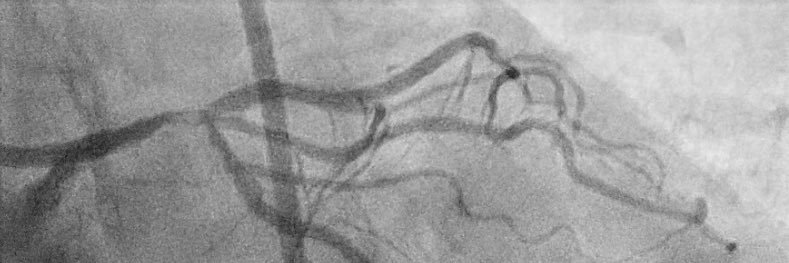

Bicuspid anatomy can pose a significant challenge for TAVI: the combination of a substantial AVC calcium burden and a prominent raphe may define a particularly high risk phenotype. #JACCImaging authors.elsevier.com/a/1mo9j,i2Xs4E…